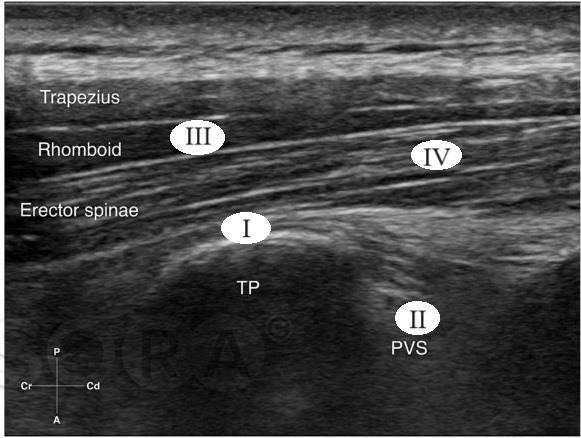

A imagem sonográfica a seguir corresponde a um bloqueio do plano do eretor da espinha, do inglês the erector spinae plane block ou, simplesmente, ESPBlock, classicamente descrito ao nível de T5, que faz parte do arsenal terapêutico do anestesiologista.

Legenda: TP – Processo Transverso; PVS – Espaço Paravertebral.

Fonte: Cangiani (2021).

Considerando a figura, o local correto de administração do anestésico, nessa abordagem, e os músculos que compõem a musculatura eretora da espinha, ao nível do tórax, respectivamente, são: